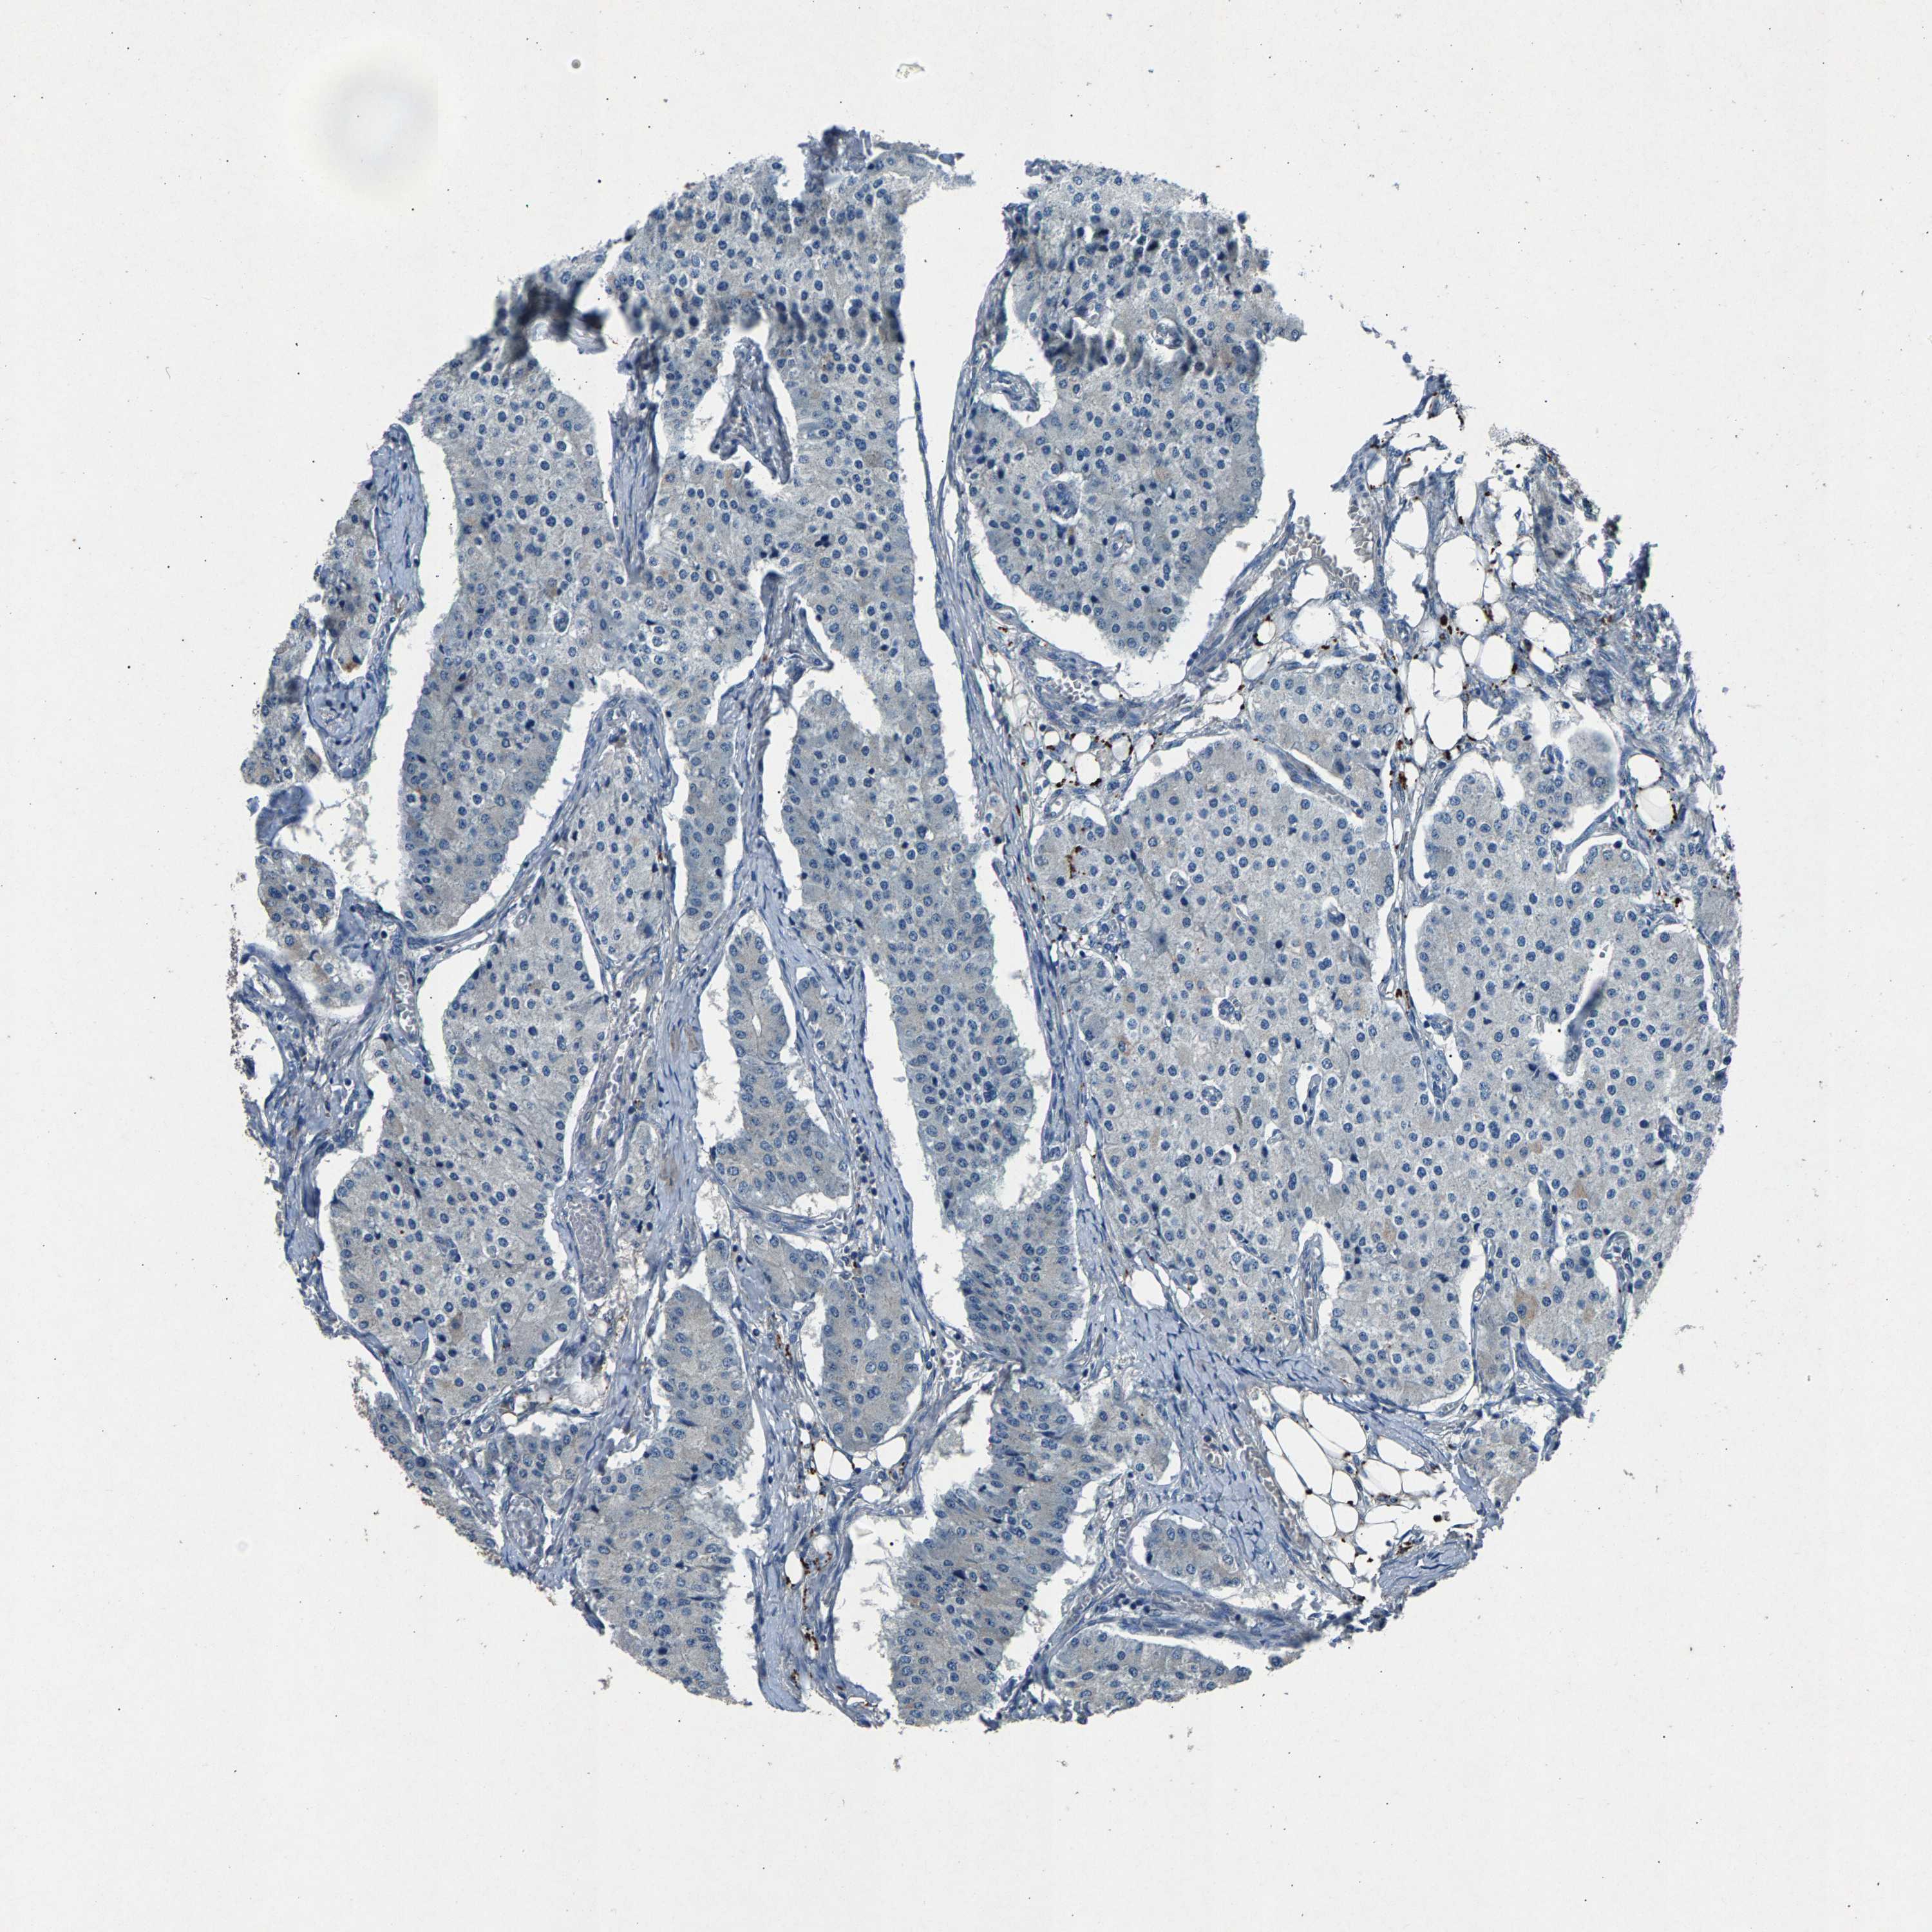

CARCINOID - Protein expressioni

A mouse-over function shows sample information and annotation data. Click on an image to view it in a full screen mode. Samples can be filtered based on level of antibody staining by selecting one or several of the following categories: high, medium, low and not detected. The assay and annotation is described here.

Antibody stainingi

Antibody staining in the annotated cell types in the current human tissue is reported as not detected, low, medium, or high, based on conventional immunohistochemistry profiling in selected tissues. This score is based on the combination of the staining intensity and fraction of stained cells.

Each image is clickable and will lead to virtual microscopy that enables deeper exploration of all samples and also displays staining intensity scores, fraction scores and subcellular localization as well as patient and tissue information for each sample.

Antibody HPA021294

Staining

High

Medium

Low

Not detected

Intensity

Strong

Moderate

Weak

Negative

Quantity

>75%

75%-25%

<25%

None

Location

Nuclear

Cytoplasmic/membranous

Cytoplasmic/membranous,nuclear

Carcinoid, malignant, NOS

Carcinoma, NOS